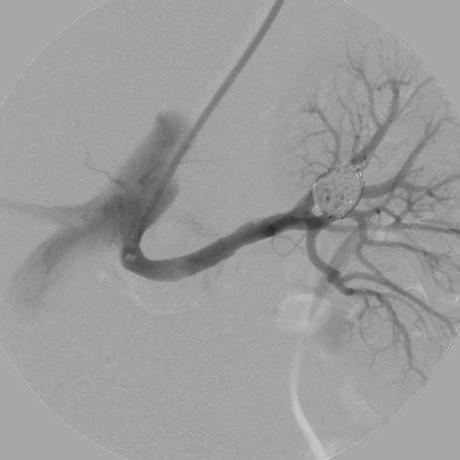

We describe the successful use of a new neurointerventional coil to treat an enlarging wide-necked segmental-branch renal aneurysm in an elderly woman who was not a candidate for surgery because of several comorbidities.

The technique described allowed safe, successful treatment of a wide-necked aneurysm in an unfavorable vascular territory, reducing the risk of downstream artery embolization and consequent parenchymal damage and decreased renal function. In similar cases, other endovascular devices have often proven to be ineffective at nephron sparing. To validate the safety and efficacy of this system, more cases treated in this manner should be studied.